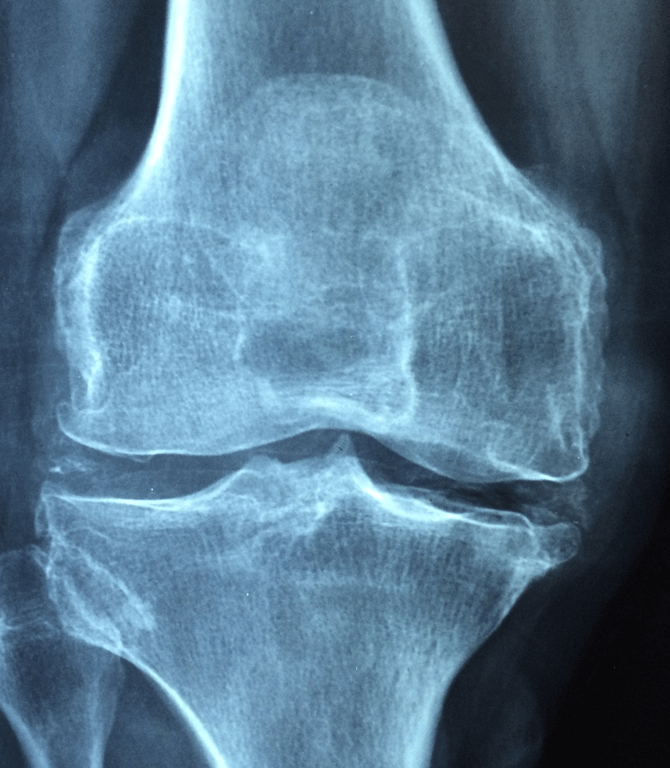

5. 골밀도의 저하

우리 몸을 지탱하는 뼈는 대부분 칼슘으로 이루어져 있습니다. 하지만 칼슘섭취가 부족할 경우 뼈의 골밀도가 낮아지게 되는데 칼슘 부족 증상으로 뼈가 푸석푸석해지고, 구멍이 많아지는 골다공증이 발생하기 쉬워집니다. 우리 몸은 30대 이전에는 칼슘의 축적량이 많아 뼈에 칼슘을 쌓아두어 튼튼하게 해 주지만, 40대 이후에는 축적량보다 분해량이 더 많기 때문에 뼈가 약해지게 됩니다.